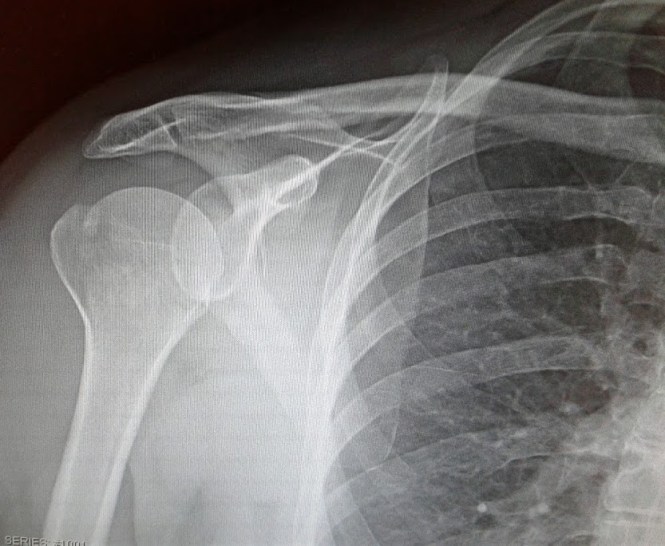

This is a photo of an x-ray of my broken right shoulder. Minnesota Prairie Roots file photo May 2017.

I’m not surprised by my good test results. I grew up on a dairy farm and have always consumed plenty of dairy products. I lift weights. And I fell in such a way that anyone—strong bones or not—would have suffered a fracture. And, yes, that includes my May 2017 fall on a hospital stairway in which I slammed shoulder first onto a concrete floor. I defy anyone not to break a bone when propelling into a surface like that. I’m thankful I didn’t hit my head, resulting in a concussion and/or broken neck.